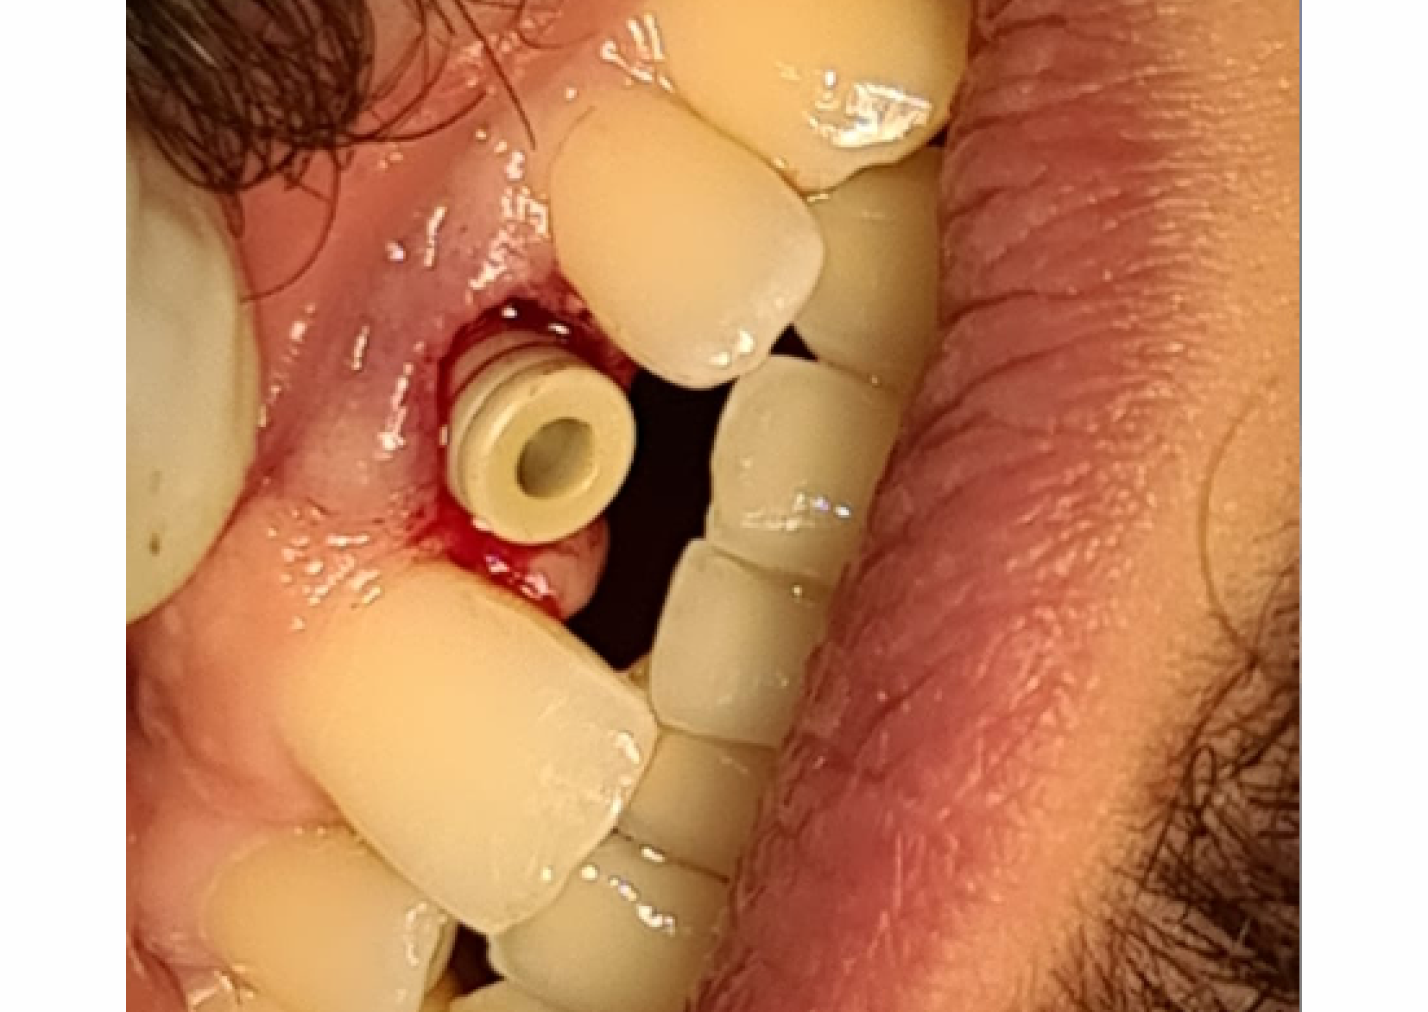

Immediate loading of dental implants, particularly in the aesthetic zone, poses unique challenges and requires meticulous planning to ensure successful outcomes. This case report presents the management of a male patient requiring aesthetic zone restoration through Naxis implant placement with simultaneous restoration following tooth fracture.